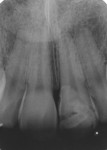

An 18-year-old male patient presented with a visible fracture in the left upper central incisor (tooth No. 9) due to a skateboard accident (Figure 1). The patient did not complain of pain. After the clinical examination, the clinician diagnosed an oblique root-crown fracture of enamel and dentin, with the involvement of the periodontal biologic space but without pulp exposure and mobility (Figure 2). The injury resulted in two dental fragments that were presented by the patient. The fragments were in good condition; they had been properly cleaned and stored in a saline solution for approximately 10 hours, and, in the examination, they adapted to the remaining tooth (Figure 3). The examination, including sensitivity and percussion tests, and the radiographic exams showed normal periapical and periodontal tissues, which gave the appearance of vitality to the damaged tooth, eliminating the need for endodontic treatment (Figure 4 and Figure 5). Thus, since there was no pulp exposure it was proposed to perform only the indirect pulp capping of the pulp-dentin complex, as this was the least invasive approach. The patient was informed about the risks and advantages of the treatment and consented to it.

After 15 days (Figure 16 and Figure 17), the patient was re-evaluated, and the stability of color between the fragment and the remainder was verified. In order to improve the esthetics of the case, the clinician decided to conduct a reduction and resin restoration on the fragment–tooth interface. The reduction on the fragment–tooth interface was performed using a round diamond 1012 (KG Sorensen) and the restoration was filled with composite resin (Filtek Z350) in the selected color, A2, including both dentin and enamel. Finishing and polishing were carried out with a combination of abrasive sanding discs (Sof-Lex Pop-On™, 3M ESPE), rubber abrasive (Astropol Ivoclar Vivadent, www.ivoclarvivadent.com), and felt disc (FGM Dental Products, www.fgm.ind.br) with diamond paste. The result can be seen in Figure 18, immediately after the restorative treatment, and in Figure 19 and Figure 20, at a clinical follow-up of 6 months.